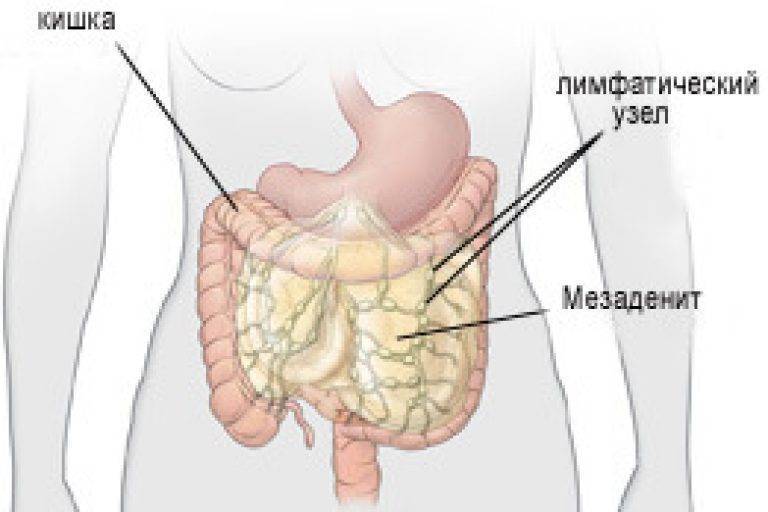

Мезентериальные лимфатические узлы: УЗИ и диагностика